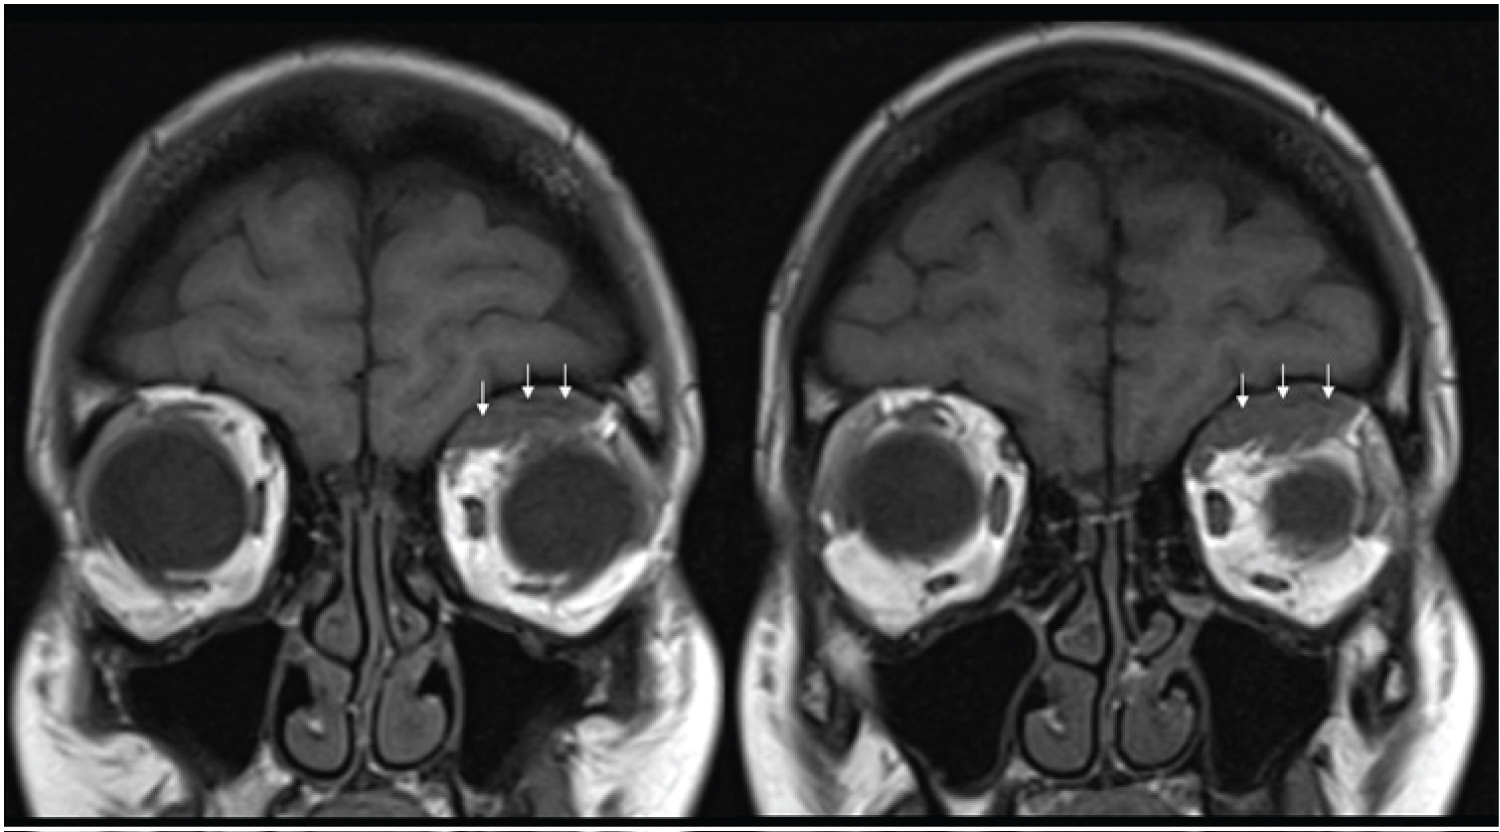

A 34-year-old healthy woman, gesta2 para1, was admitted, at term (39 weeks and 4 days) in our obstetric unit on spontaneous labor. There were no reported complications during the pregnancy and labor developed uneventfully, with normal duration and evolution. Vaginal delivery of a female newborn with normal weight (3160 grams) occurred without need of medical instrumentation. During final expulsive efforts, the mother complained of left ocular pressure and, after delivery, the feeling of double vision. On physical examination, she had an orbital asymmetry with left eye proptosis and inferior deviation. Ophthalmological examination revealed a left vertical diplopia with normal visual acuity (10/10, bilaterally). Pupils were reactive and there was no papilledema. Orbital CT diagnosed a homogeneous, hyperdense lesion with 6.5 × 25 × 34 mm on the left upper orbit, suggestive of hematoma (Figure 1). Orbital/cranial MRI, performed two days later, confirmed an intraorbital, extra-conic acute hematoma with 7 mm (maximum diameter), imposing inferior deviation of left ocular globe (Figure 2). Expectant management was adopted and no other clinical complains were registered.

Figure 2: Hematoma on the left upper orbit (white arrows) on cranial MRI. View Figure 2